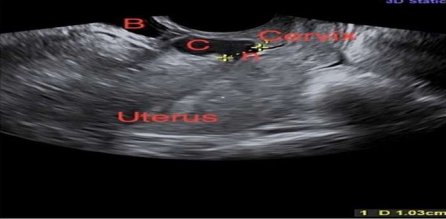

Figure 2 2-D ultrasound showing uterus, cervix, niche (n) measuring 1 cm, collection in the niche (C) and bladder (B) (courtesy Prof. Vatsla Dadhwal)